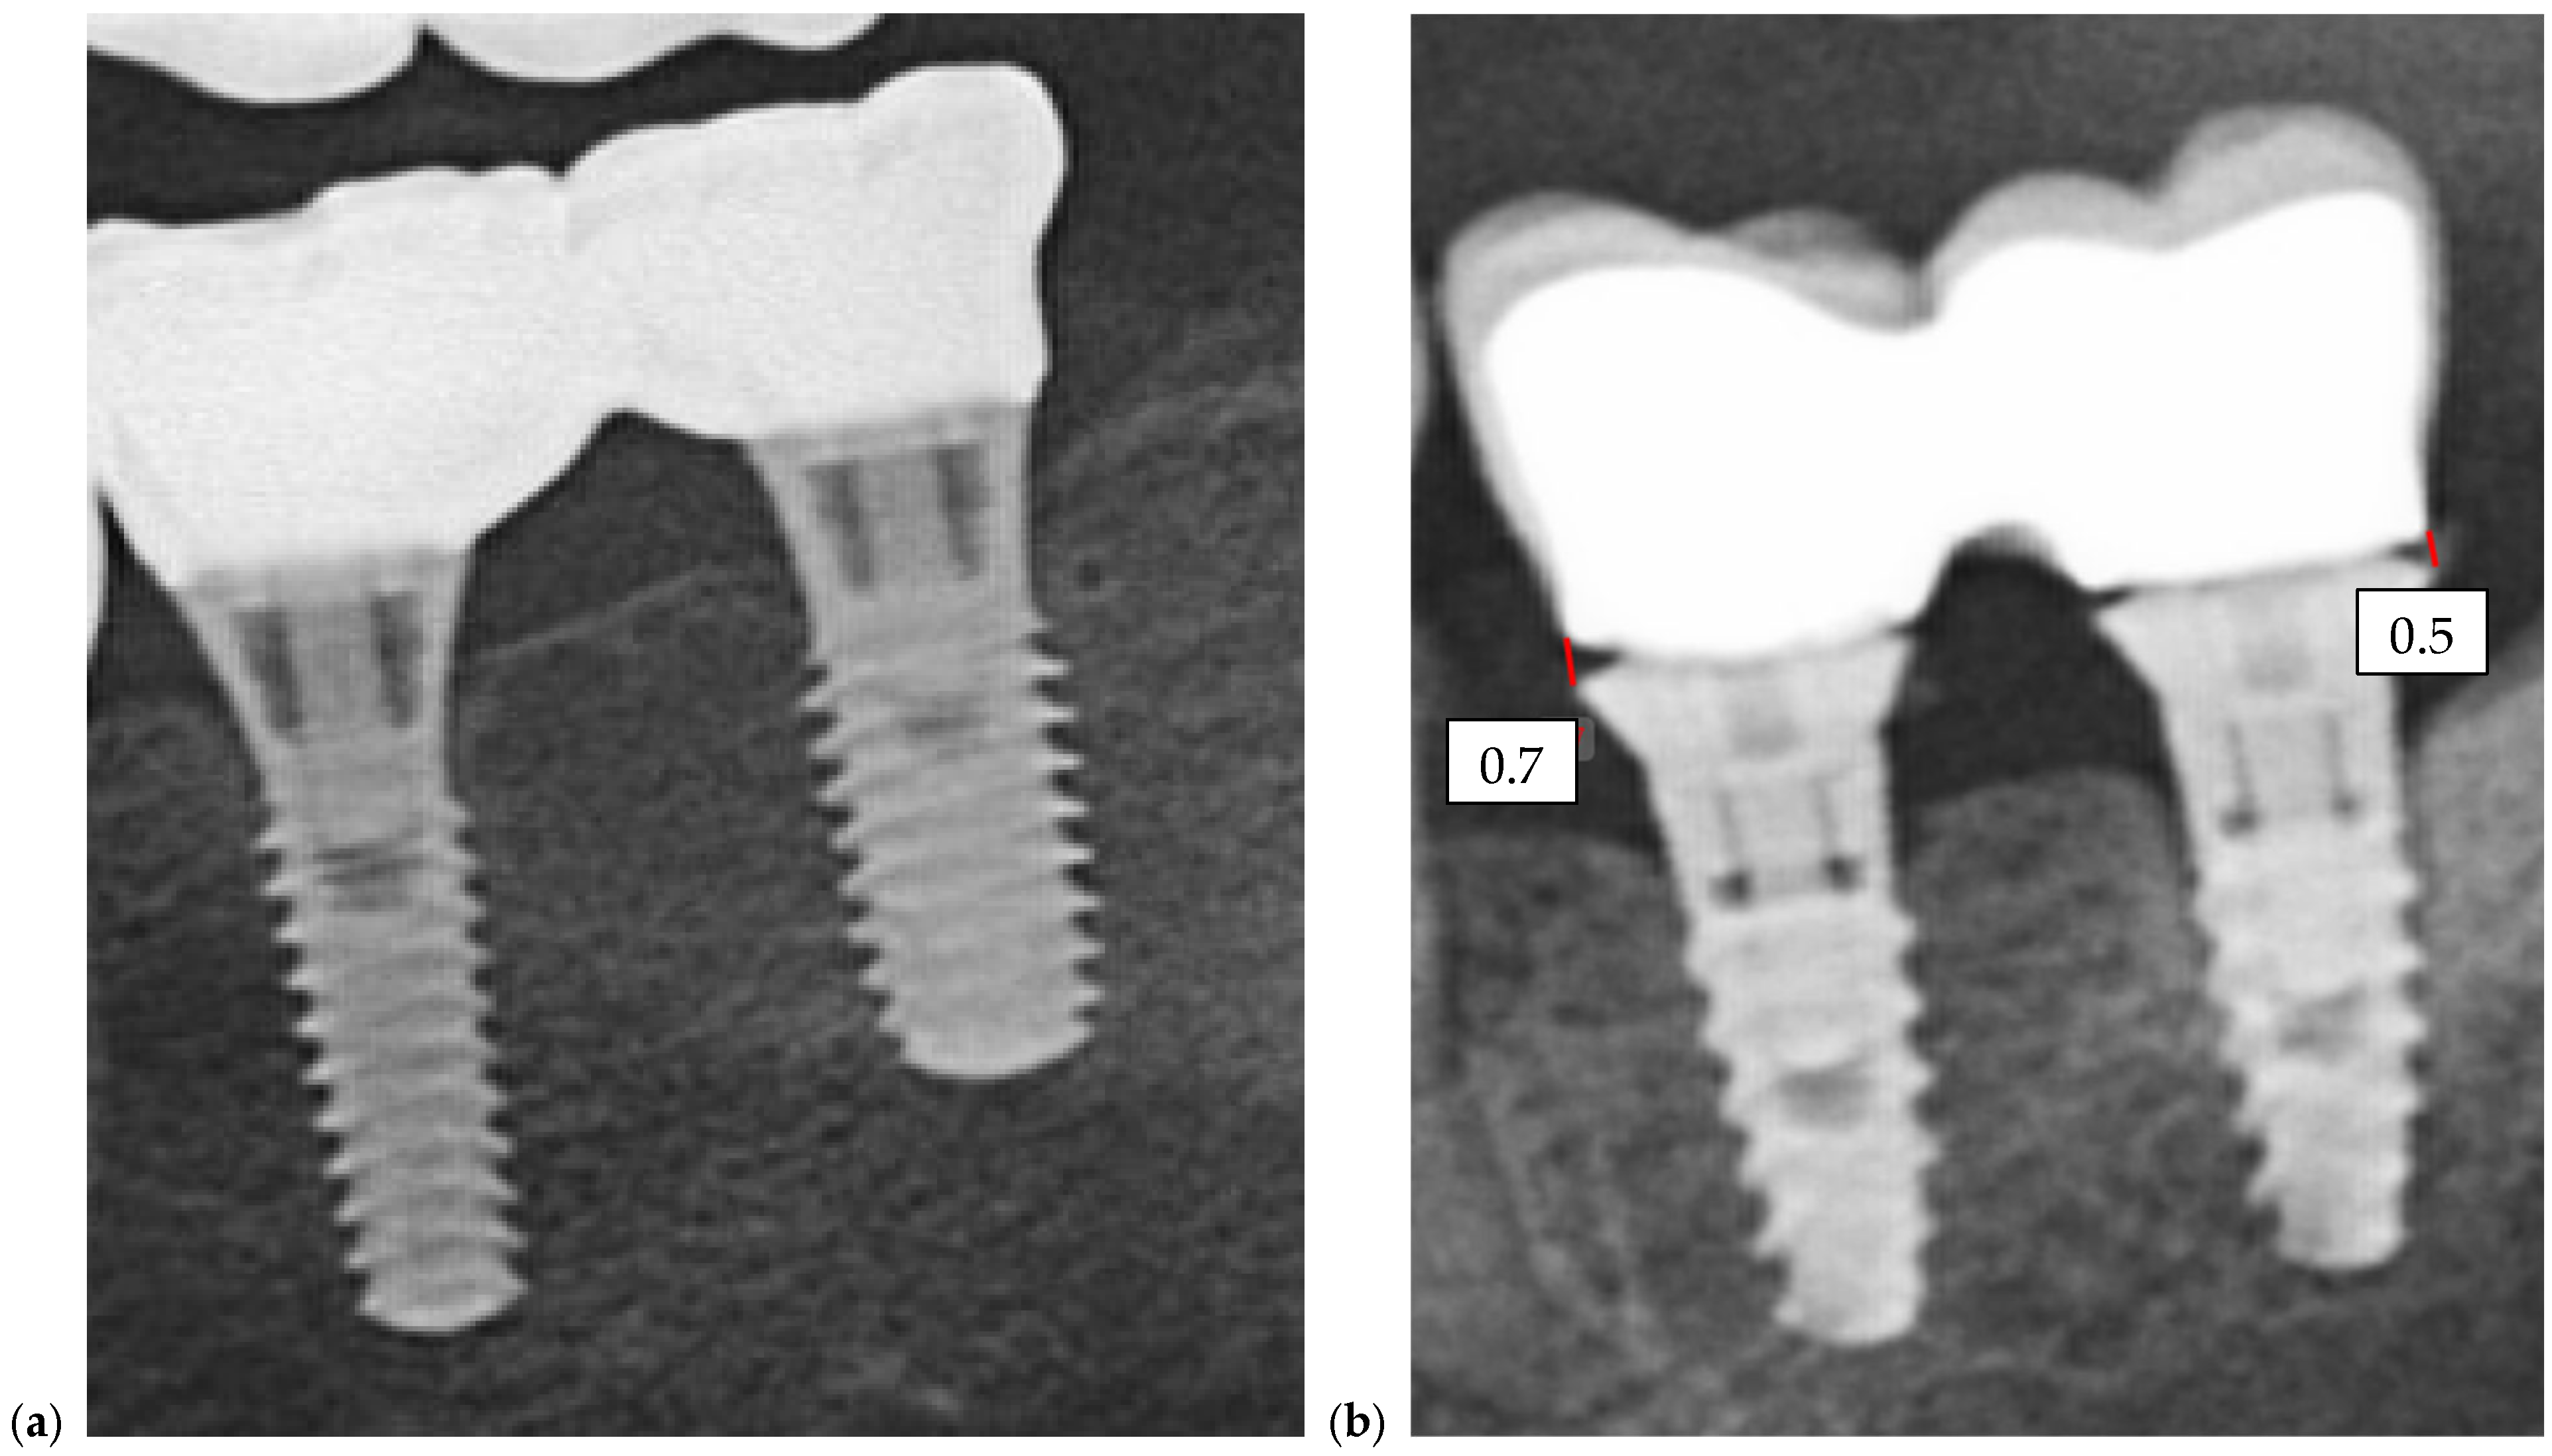

Radiographic assessments were conducted during the initial impression phase, provisional restoration try-in, and final prosthesis delivery. CBCT, panoramic radiographs, and intraoral periapical radiographs were used to visualize the implant–abutment interface and prosthetic fit. All imaging was performed using standardized exposure parameters, with radiographs analyzed using calibrated digital imaging software to assess marginal gaps and seating accuracy. In Figure 6, a representative case is presented, illustrating the radiographic sequence from the patient’s initial visit to the annual follow-up appointments. Figure 6a shows the panoramic radiograph (OPG) obtained at the first visit. Figure 6b corresponds to the postoperative image taken immediately after implant placement. Figure 6c illustrates the situation six months after surgery, following the delivery of the temporary restoration. Figure 6d shows the radiograph taken six months after provisional restoration was delivered, immediately after delivery of the definitive restorations. Figure 6e–i represent the annual recall examinations. Vertical marginal discrepancies were quantified as linear distances in millimeters (mm) at the implant–abutment interface. All radiographic examinations (periapical, panoramic, or CBCT) included in the analysis were obtained strictly for clinical diagnostic and follow-up purposes according to standard treatment protocols. No supplementary exposures were performed for research reasons. Data were analyzed retrospectively from existing clinical records. Impression procedure duration was recorded in minutes (min). Patient-reported outcomes were collected as Visual Analog Scale (VAS) scores on a 1–10 scale (dimensionless) (Appendix A). The same diagnostic criteria were applied across both digital and conventional groups to ensure consistency.

Quantitative comparison of marginal discrepancies was performed using radiographic measurements at the implant–abutment interface (Figure 7b). The presence of vertical gaps, angular misalignments, or overextensions was noted and compared between groups.

Figure 7. OPGs of (a)—case with a perfect fit and (b)—case with misfit of 0.7 and 0.5 mm on implants from position 3.6, respectively, 3.7.

Prosthesis 07 00135 g007